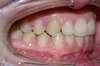

Vues avant le traitement